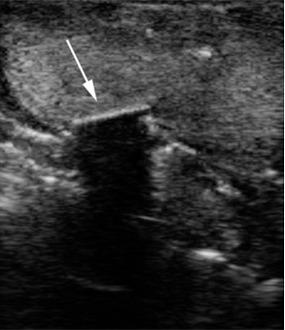

Wood and plastic foreign bodies were demonstrated more clearly on ultrasonography images. High density materials such as metal, stone, and glass were detected with almost the same accuracy on CT and ultrasonography examinations. Visibility of the foreign bodies deteriorated on ultrasonography images as their depth increased; however, CT appearances of the foreign particles were not influenced by their depths.

Ultrasonography is an appropriate technique for detection of foreign bodies especially the ones with low density. Therefore, it seems logical to perform ultrasonography in combination with CT in cases with the suspicion of foreign body impaction.